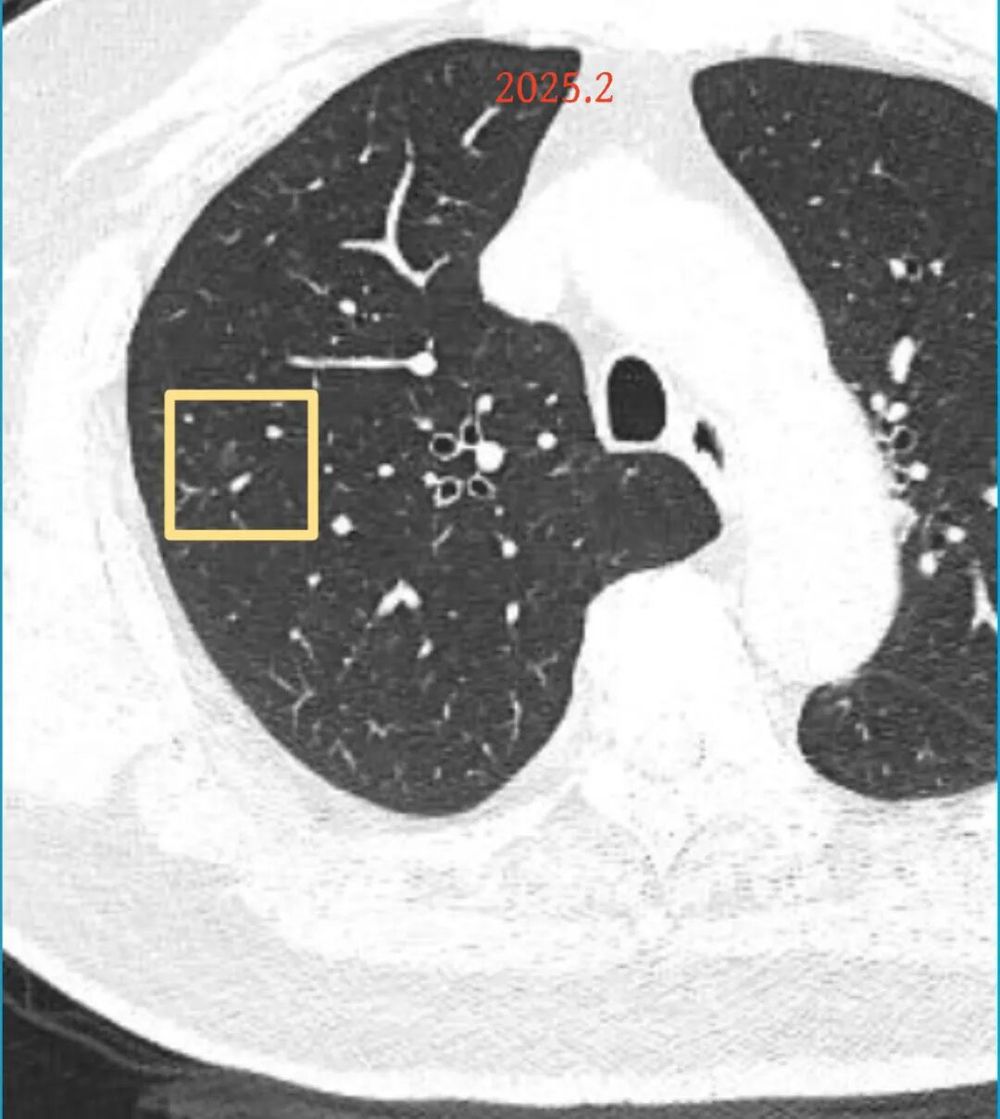

影像展示与分析:

方形的是25年的,红色的主病灶,磨玻璃密度伴少许略偏高点密度,但还说不上典型混合磨玻璃病灶,考虑原位癌或微浸润性腺癌可能性大;蓝色的轮廓与边界欠清,位置靠上叶中央,无法段切或楔切;黄色的多发均淡而纯,分布在两肺。圆形粉色的是主要的两处23年时的样子,对比说不上很明显进展。鉴于若手术得切肺叶,何况两肺他处仍的结节,年纪又74了。我倾向保守点,先6-9个月复查,等进展并风险增加再来考虑怎么办的事。意见供参考!

影像展示与分析:

病灶B似乎灶内有少许密度略偏高,但瘤肺边界欠清晰,总体说不上太显著的进展。

当时结友自己还觉得有点实性成分,血管感觉也有增粗。而我觉得整体密度仍是磨玻璃,轻微的变化仍不足以影响临床决策的程度。